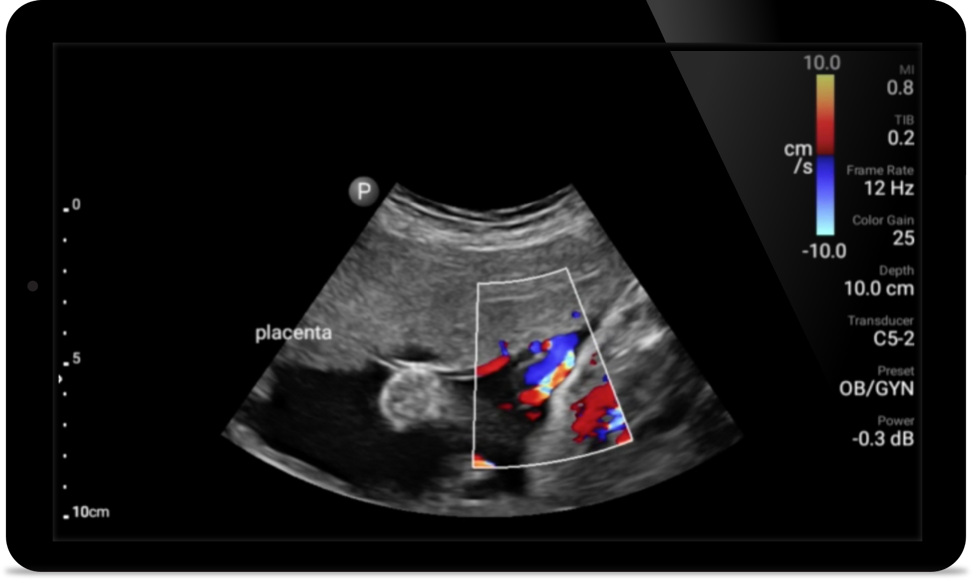

Focused renal ultrasound